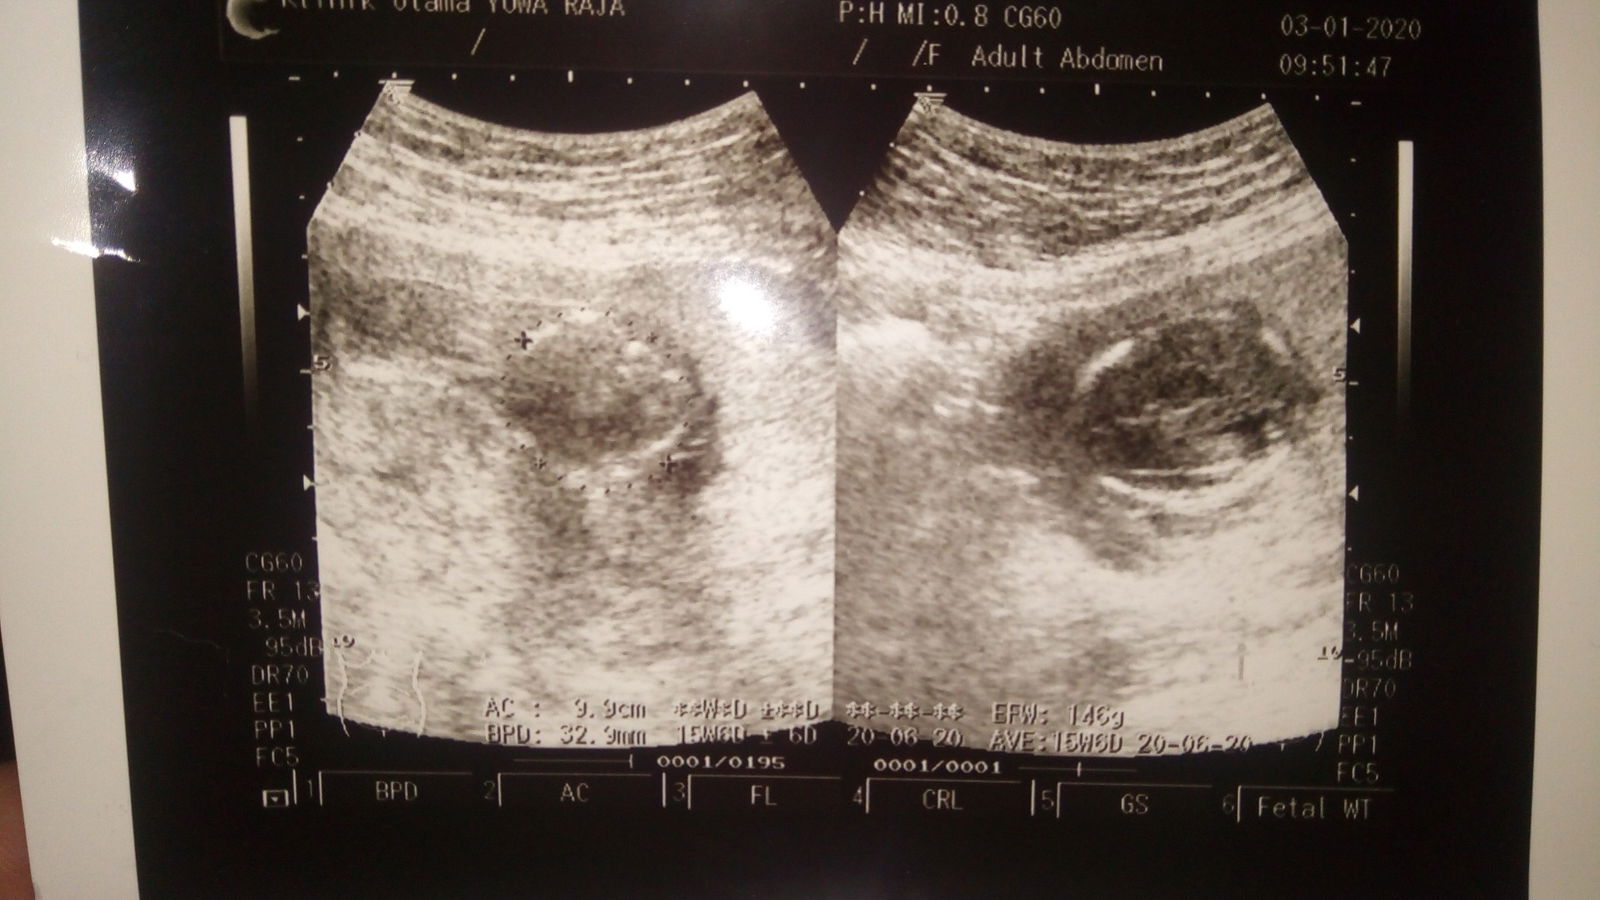

normal gak?

Was.was nih bunda.. 16 week hasil usg nya, mau tanya normal gk untuk ukuran segitu, soal nya kata temen2 aku, ko kecil bangeett kan jadi gak karuan fikiran nya, sehat apa gak nya..???